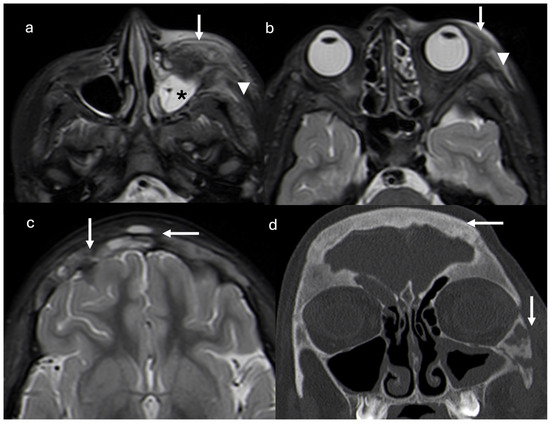

The follow-up CT scan showed lytic lesions at the frontal and zygomatic bones, and a magnetic resonance imaging (MRI) scan was required. One month after discontinuation of antibiotic therapy, MRI revealed a diffuse mucosal thickening of the left maxillary sinus, periorbital adipose tissue inflammation, pre-septal cellulitis, temporal and masseter muscle edema, and thickening and diffuse signal alterations of frontal bone with epicranic soft tissue involvement (Figure 2).

Figure 2.

Axial short tau inversion recovery (STIR) magnetic resonance images show diffuse mucosal thickening of left maxillary sinus (asterisk), periorbital adipose tissue inflammation and pre-septal cellulitis (arrows), and temporal and masseter muscle edema (arrowheads) (a,b). Thickening and diffuse signal alterations of frontal bone with epicranic soft tissue involvement (arrows) are demonstrated (c). Coronal reconstruction CT scan (d) confirmed thickening on frontal and zygomatic bones with lytic areas. Right frontal and left maxillary sinus inflammation is present (arrows).